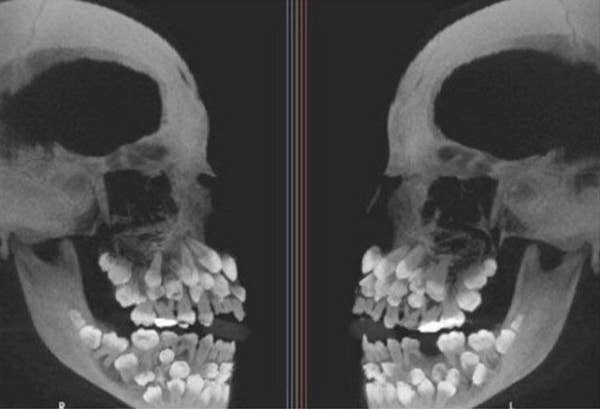

3. Знаете ли вы, что можно иметь кучу лишних зубов? Это называется гипердонтией, и часто это означает всего лишь несколько лишних зубов — показанный на снимке случай является экстремальным

4. Еще немного гипердонтии